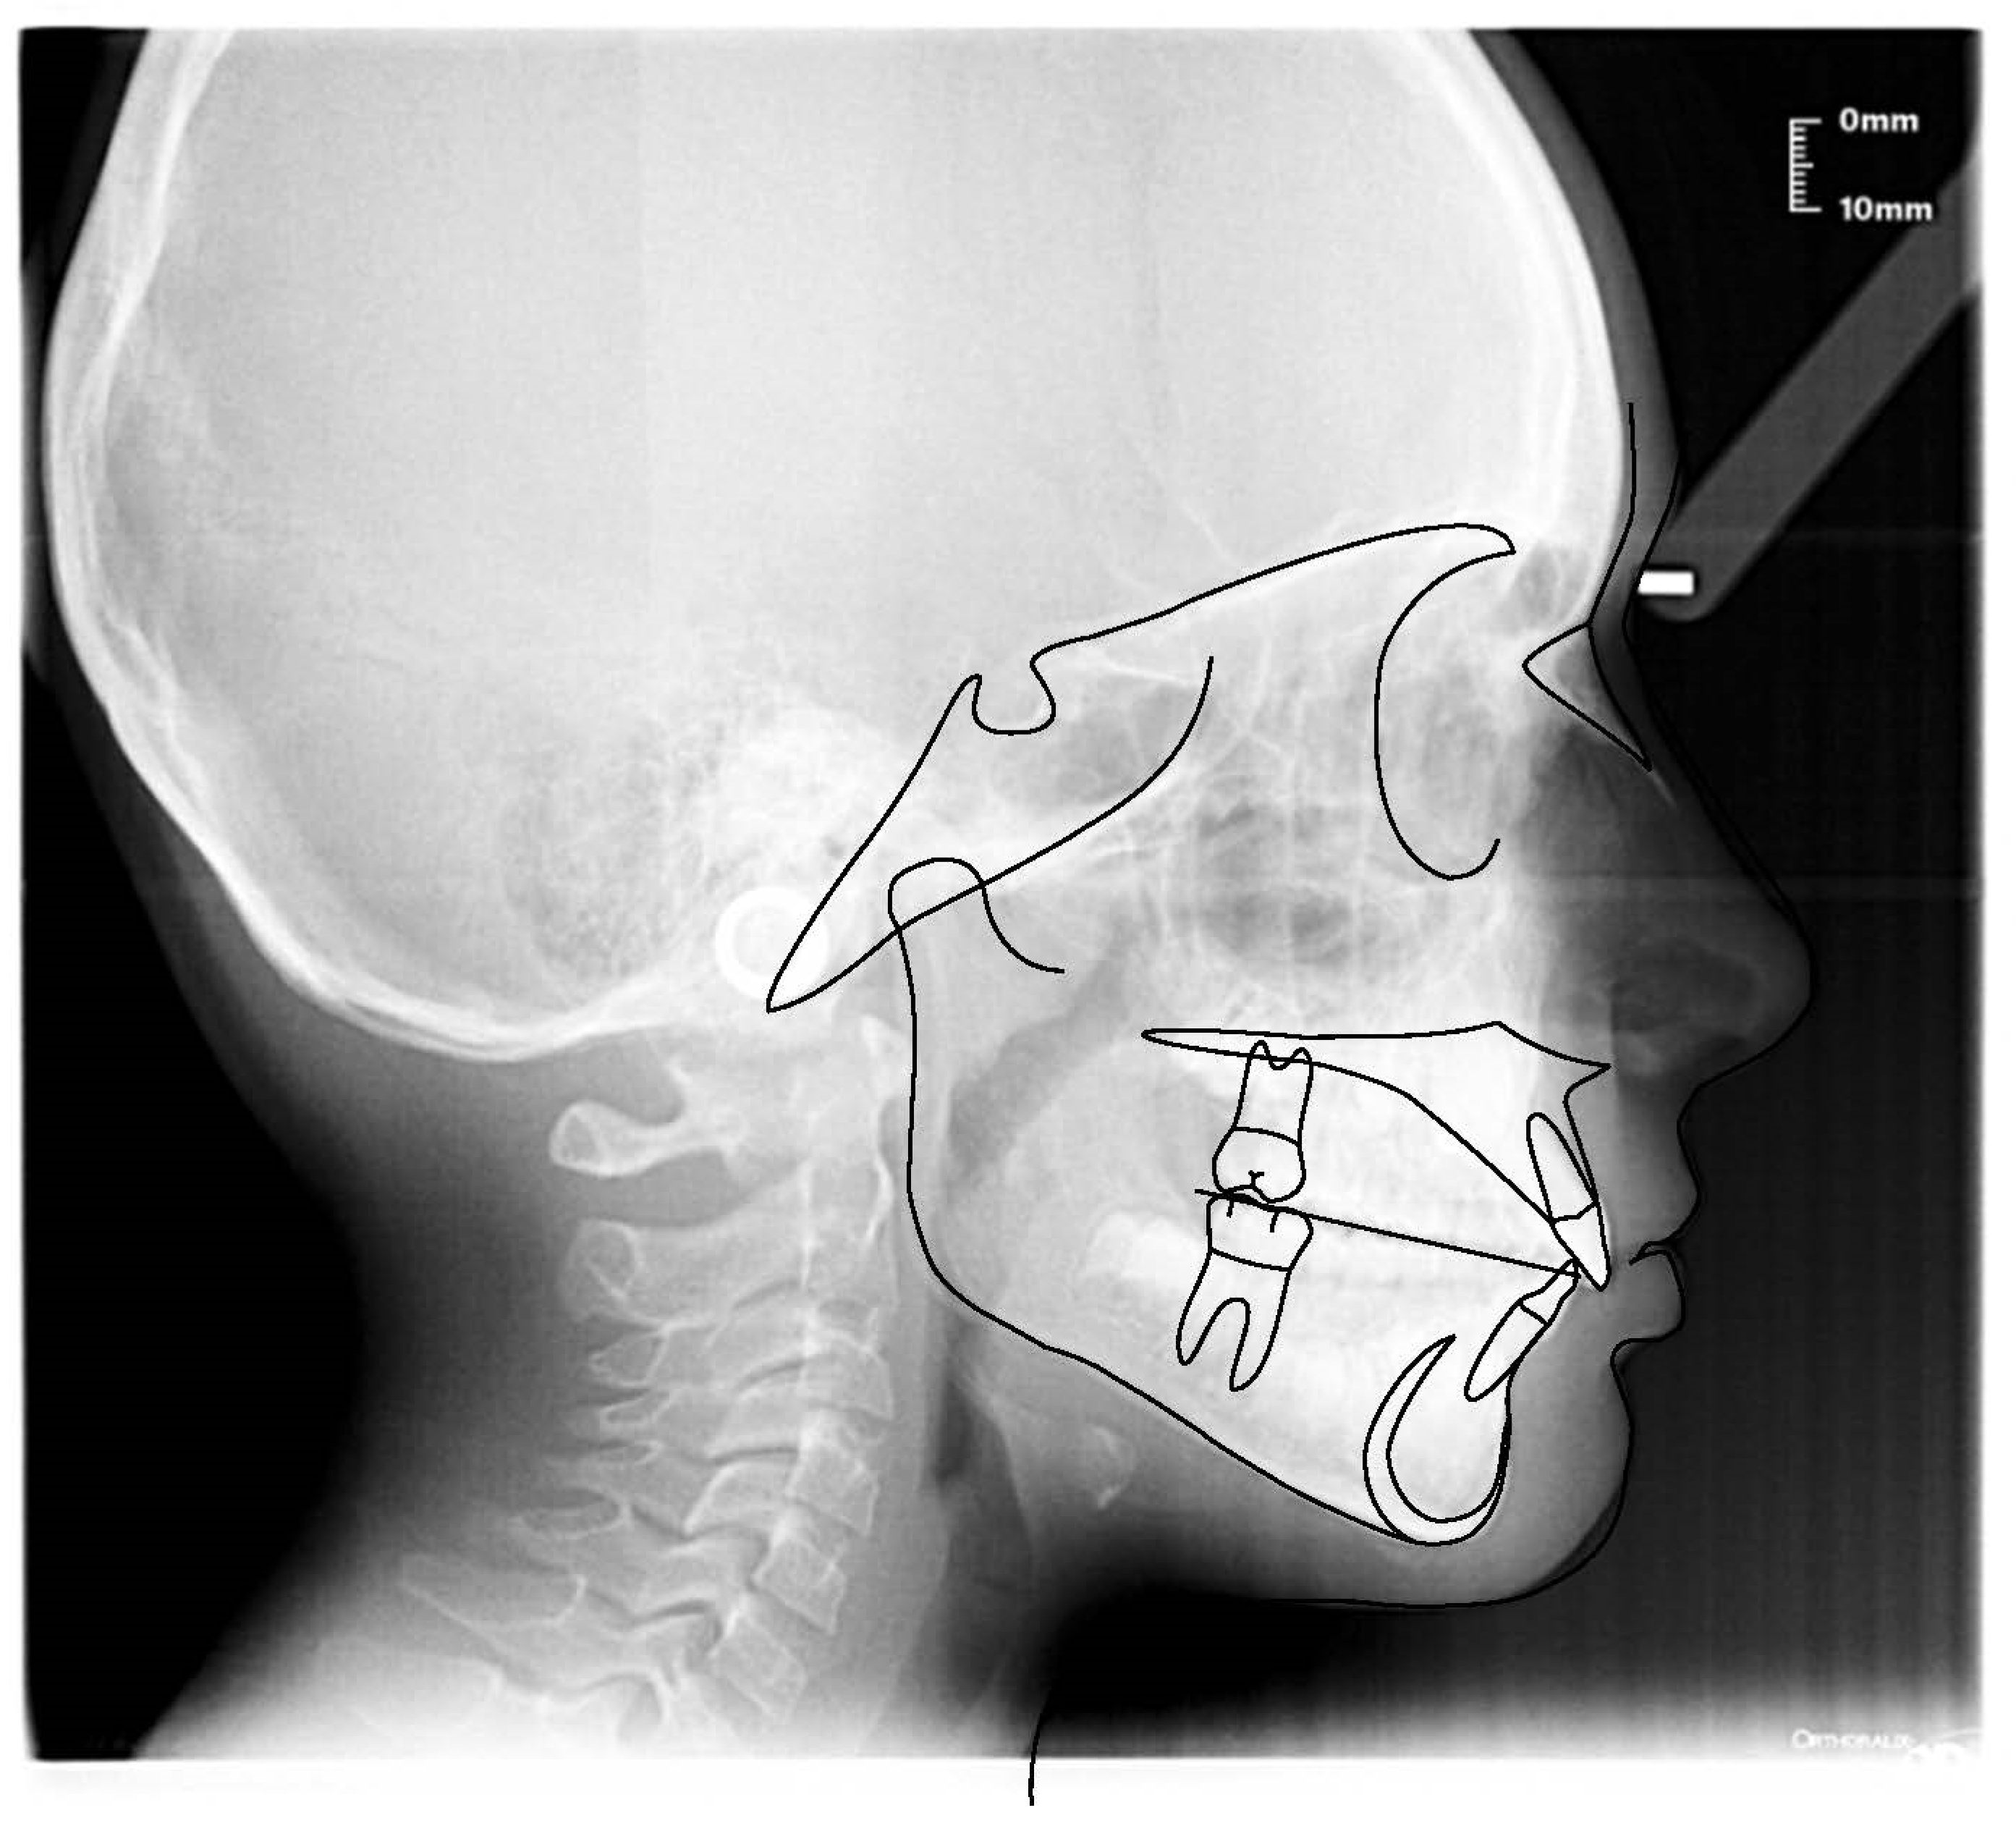

3.1. Clinical Case #1

| Cephalometric Analysis before Treatment | Val | Dev | Min | Med | Max | Diff |

|---|---|---|---|---|---|---|

| SNA | 82° | N | 80° | 82° | 84° | 0° |

| SNB | 78.6° | N | 78° | 80° | 82° | 0° |

| ANB | 3.4° | N | 0° | 2° | 4° | 0° |

| sna-snp^Go-Gn | 22.3° | N | 15° | 20° | 25° | 0° |

| S-N^sna-snp | 8.9° | N | 7° | 10° | 13° | 0° |

| S-N^PO | 14.2° | N | 11° | 14° | 17° | 0° |

| S-N^Go-Gn | 31.2° | N | 27° | 32° | 37° | 0° |

| SNBa | 136.6° | x | 124° | 129° | 134° | 2.6° |

| SND | 75.1° | N | 74° | 76° | 78° | 0° |

| IS^II | 128.9° | N | 125° | 130° | 135° | 0° |

| IS:N-A | 3.5 | N | 3 | 4 | 5 | 0 |

| II:N-B | 3.7 | N | 3 | 4 | 5 | 0 |

| II:A-Pog | 1.7 | N | −1 | 1 | 3 | 0 |

| Ls:Line S | −2.1 | −xx | −1 | 0 | 1 | 1.1 |

| Li: Line S | 0.4 | N | −1 | 0 | 1 | 0 |

| Cvm:S-Gn | −3.4 | −xxx | −1 | 0 | 1 | 2.4 |

| Mol Sup^P. Occl | 99.5° | xxxx | 88° | 90° | 92° | 7.5° |

| N-S-Cop | 135.2° | xx | 117° | 122° | 127° | 8.2° |

| S-Cop-Go | 137.3° | N | 137° | 143° | 149° | 0° |

| Cop-Go-Gn | 118.7° | N | 115° | 120° | 125° | 0° |

| Cop-Go-N | 51.2° | N | 48° | 50° | 52° | 0° |

| N-Go-Gn | 67.6° | −x | 68° | 70° | 72° | 0.4° |

| II^Go-Gn | 94.1° | x | 92° | 93° | 94° | 0.1° |

| SOr:sna | 62.9 | 0 | 0 | 0 | 62.9 | |

| sna:Me | 63.7 | 0 | 0 | 0 | 63.7 | |

| S:N | 69.6 | −xx | 75 | 78 | 81 | 5.4 |

| snp:A | 54.7 | 0 | 0 | 0 | 54.7 | |

| Go:Me | 75.4 | N | 73.7 | 78.7 | 83.7 | 0 |

| Wits | 1.5 | N | −2 | 0 | 2 | 0 |

| IS^N-S | 105.9° | x | 101° | 103° | 105° | 0.9° |

| Pog:N-B | 0.9 | 0 | 0 | 0 | 0.9 | |

| Pog:N-B—II:N-B | −2.8 | - | 0 | 0 | 0 | 2.8 |